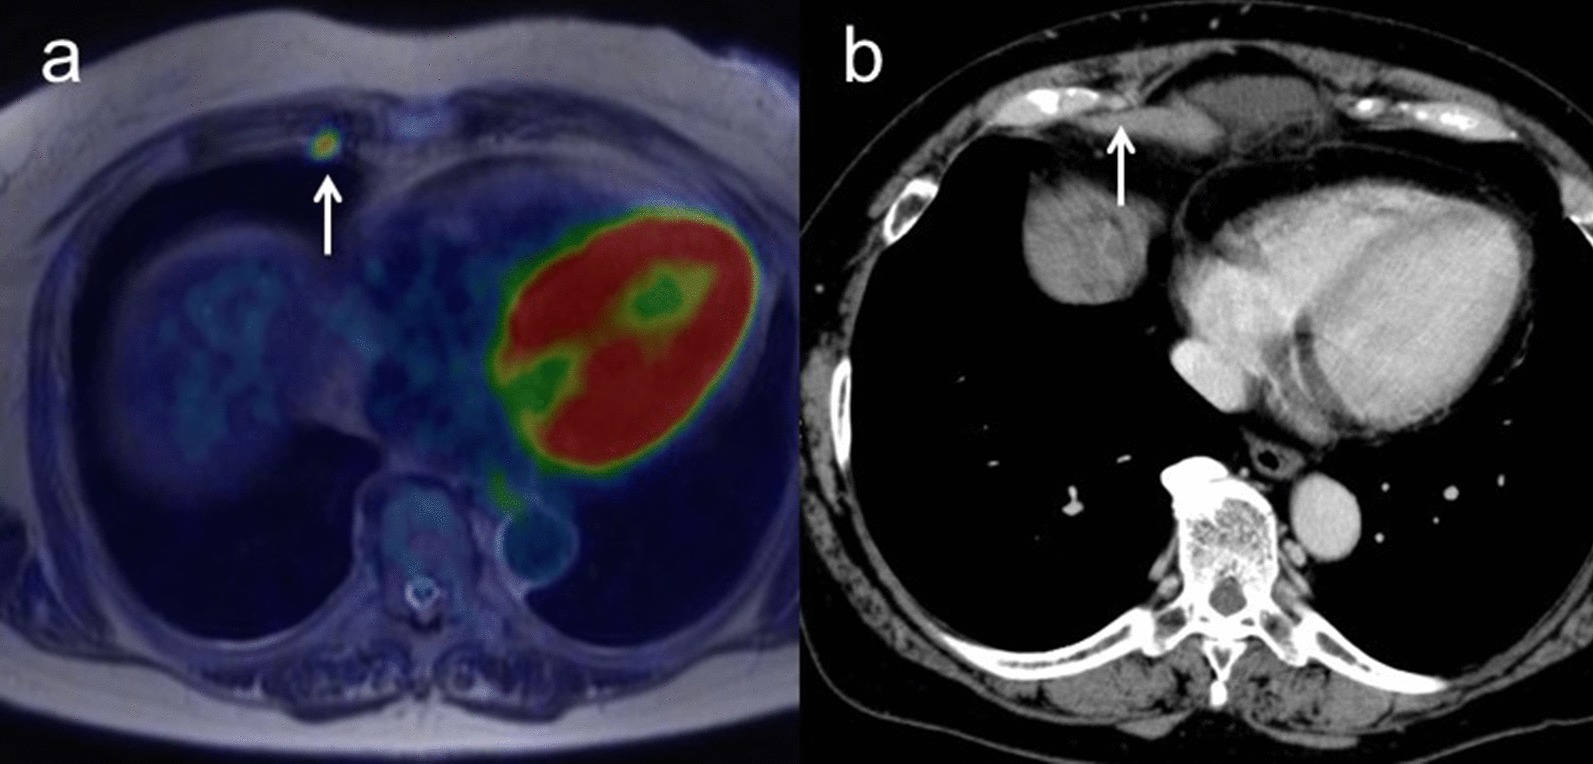

Sensitivity, specificity and accuracy for M staging were 100% (95% CI 0.94–1.00), 100% (95% CI 0.25–1.00) and 100% (95% CI 0.88–1.00) for [18F]FDG PET/MRI, and 25.0% (95% CI 0.19–0.25), 100% (95% CI 0.22–1.00) and 30.8% (95% CI 0.19–0.31) for ceCT, respectively (p < 0.01). ceCT incorrectly classified nine M1 tumors as M0 (Table 5). Figure 4 shows representative images for M staging.

Fig. 4.

a A 66-year-old woman with pathologically confirmed ovarian cancer. Axial T2-weighted PET/MR image shows a right parasternal lymph node with FDG uptake (arrow). b Contrast-enhanced CT shows a right parasternal lymph node less than 1 cm in short-axis diameter with slightly enhancement (arrow). After NAC, this lymph node decreased in size and SUV, suggesting that this node as a sign of malignancy (M1)